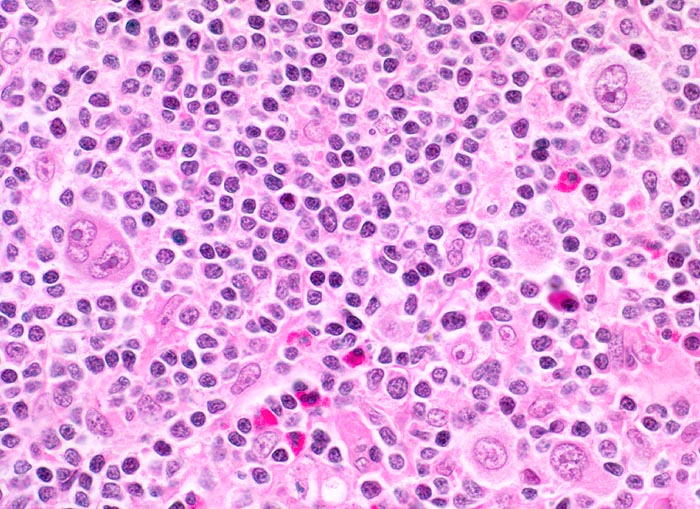

Das Zellbild ist bunt und umfasst Lymphozyten, Plasmazellen, eosinophile Granulozyten und einzeln im reaktiven Infiltrat liegende Tumorzellen. Die Tumorzellen sind einkernig (Hodgkin Zelle) oder mehrkernig (Reed-Sternbergzellen) und enthalten einen sehr grossen Nukleolus. Die Tumorzellen sind immunzytochemisch positiv für CD15 und CD30. Nodulär sklerosierender und gemischtzelliger Subtyp des Hodgkin Lymphoms sind zytologisch nicht sicher zu unterscheiden.

Gezeigt werden eine noduläre Sklerose und zwei Hodgkin Lymphome vom Mischzelltyp.